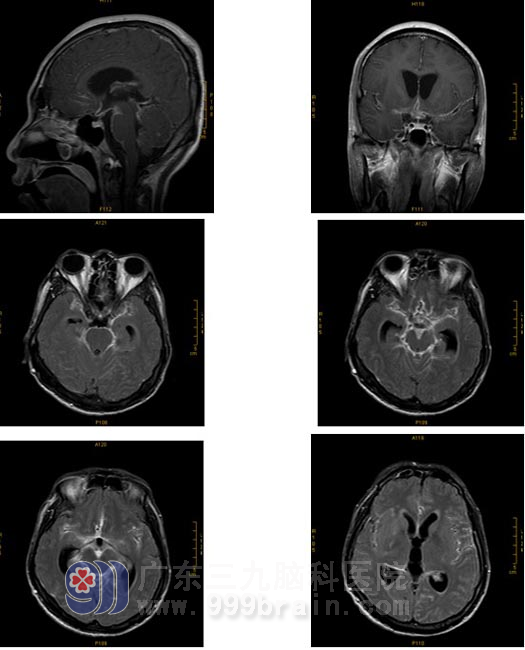

影像学表现

平扫: 双侧基底节区及双侧大脑半球皮层下白质内多发病灶,幕上轻度梗阻性脑积水。

增强扫描:基底池、桥前池及双侧外侧裂池软脑膜均可见明显强化;桥脑、小脑及双侧大脑半球可见散在的斑点状异常强化灶